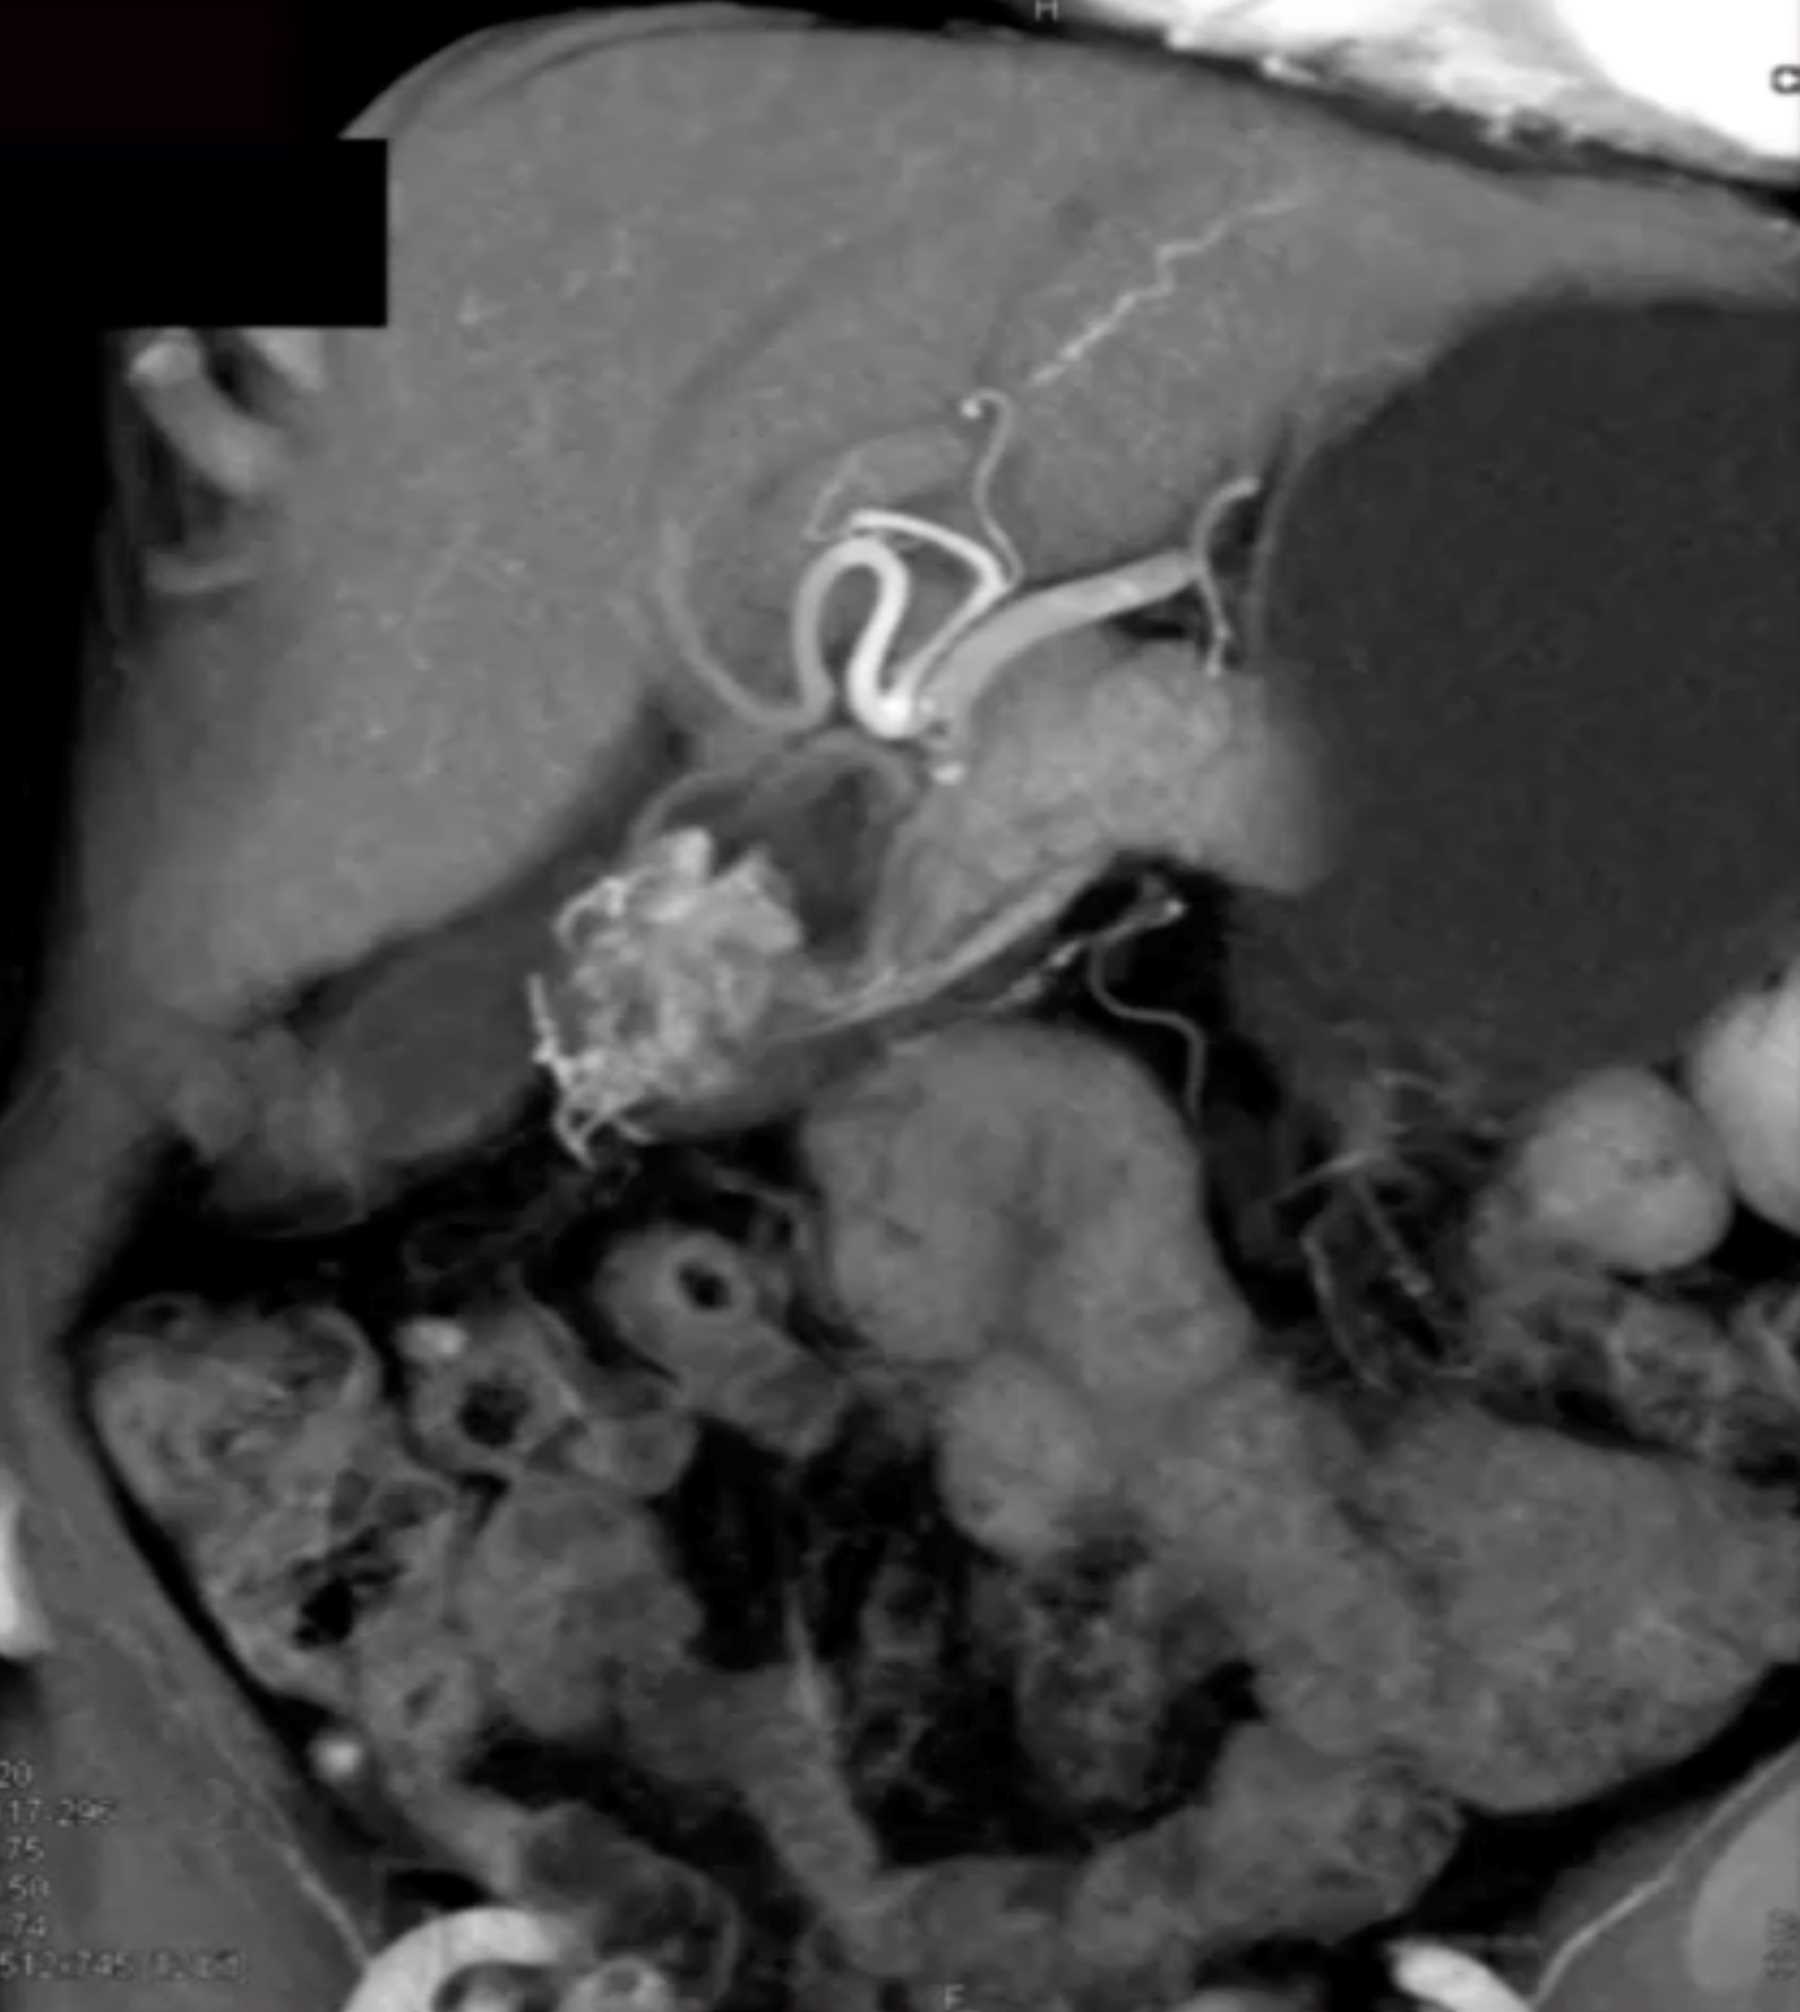

Watermelon Stomach (Gastric Antral Vascular Ectasis)